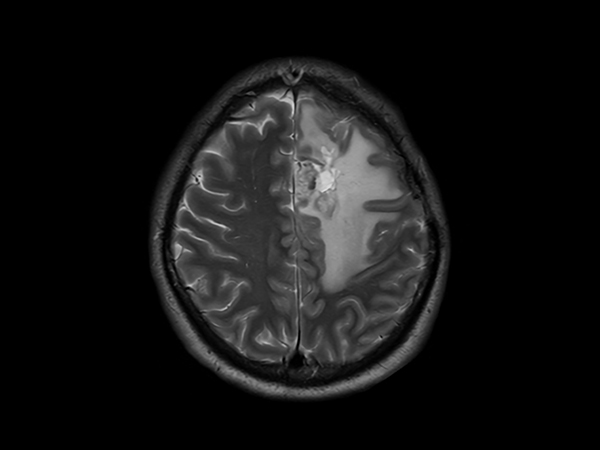

SmartSpeed Precise imaging for brain with glioblastoma

Kyushu University Hospital Japan